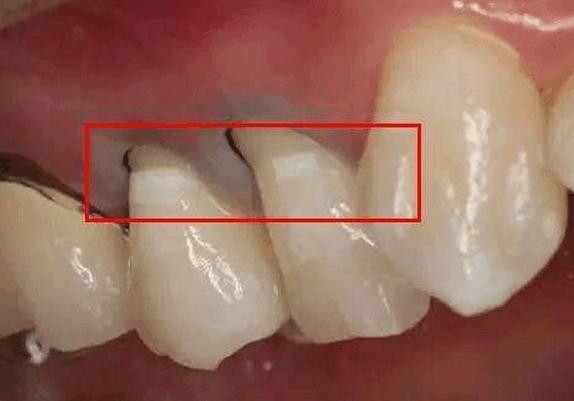

牙結石凡是存在於唾液腺啟齒處的牙齒外表(比方:下顎前牙的舌側外表,上顎后牙的頰側外表)和牙齒的頸部,還有口腔粘膜活動不到的牙齒外表等處。牙結石開始時是軟軟的,會因逐步的鈣化而變硬。它是由75%的磷酸鈣,15-25%的水、有機物、磷酸錳、礦酸鈣及微量的鉀、鈉、鐵所組成。並呈現出黃色、棕色、或許玄色。